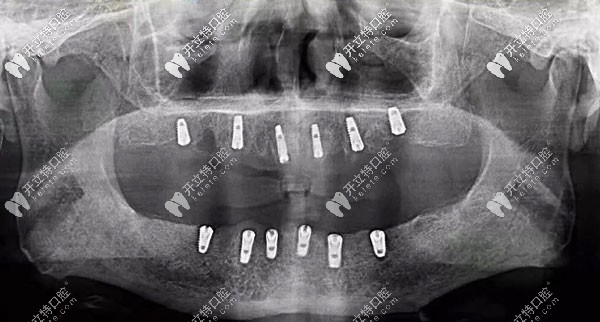

半口種植6顆牙根的全景片示意圖

all-on-6半口種植牙——只需種植6顆牙根就可以裝14個(gè)牙冠來(lái)恢復(fù)咀嚼功能哦!

也就是說(shuō)只需種植4~6顆種植體就能恢復(fù)半口14顆牙的功能,實(shí)現(xiàn)了過(guò)去半口需種14顆植體所起的作用。